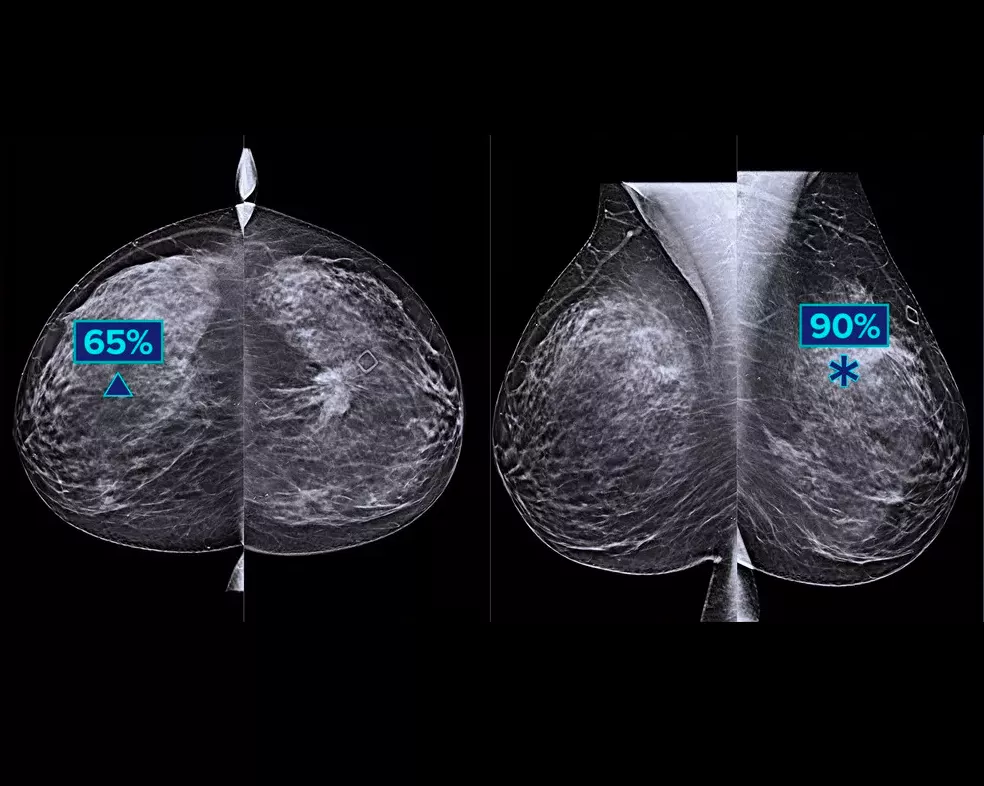

A tecnologia de aquisição de imagem Intelligent 2D com base em IA produz imagens 2D sintetizadas e robustas, mas ainda assim com um aspeto natural, que são bem relacionadas com os dados da mamografia 3D. Isto permite aos radiologistas detetar de forma rápida e com confiança características da mamografia subtis e a morfologia da lesão.*

Preserve mais características de interesse graças aos dados de mamografia 3D de alta resolução. Utilize a análise com base em IA para visualizar com confiança características do tecido subtis e lesões nas imagens 2D sintetizadas e reconstruídas.